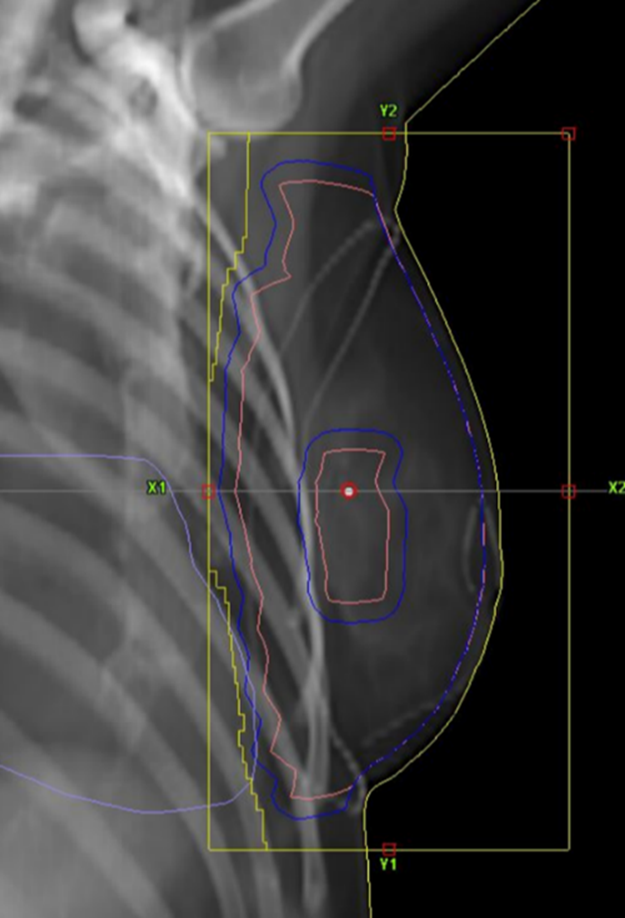

Figur 7. Exempel på BEV för ett tangentiellt strålfält.

Figur 9. Exempel på BEV för strålfält över körtelvolymen.

Figur 11. Exempel på BEV för tangentiella fält vid behandling med körtlar.